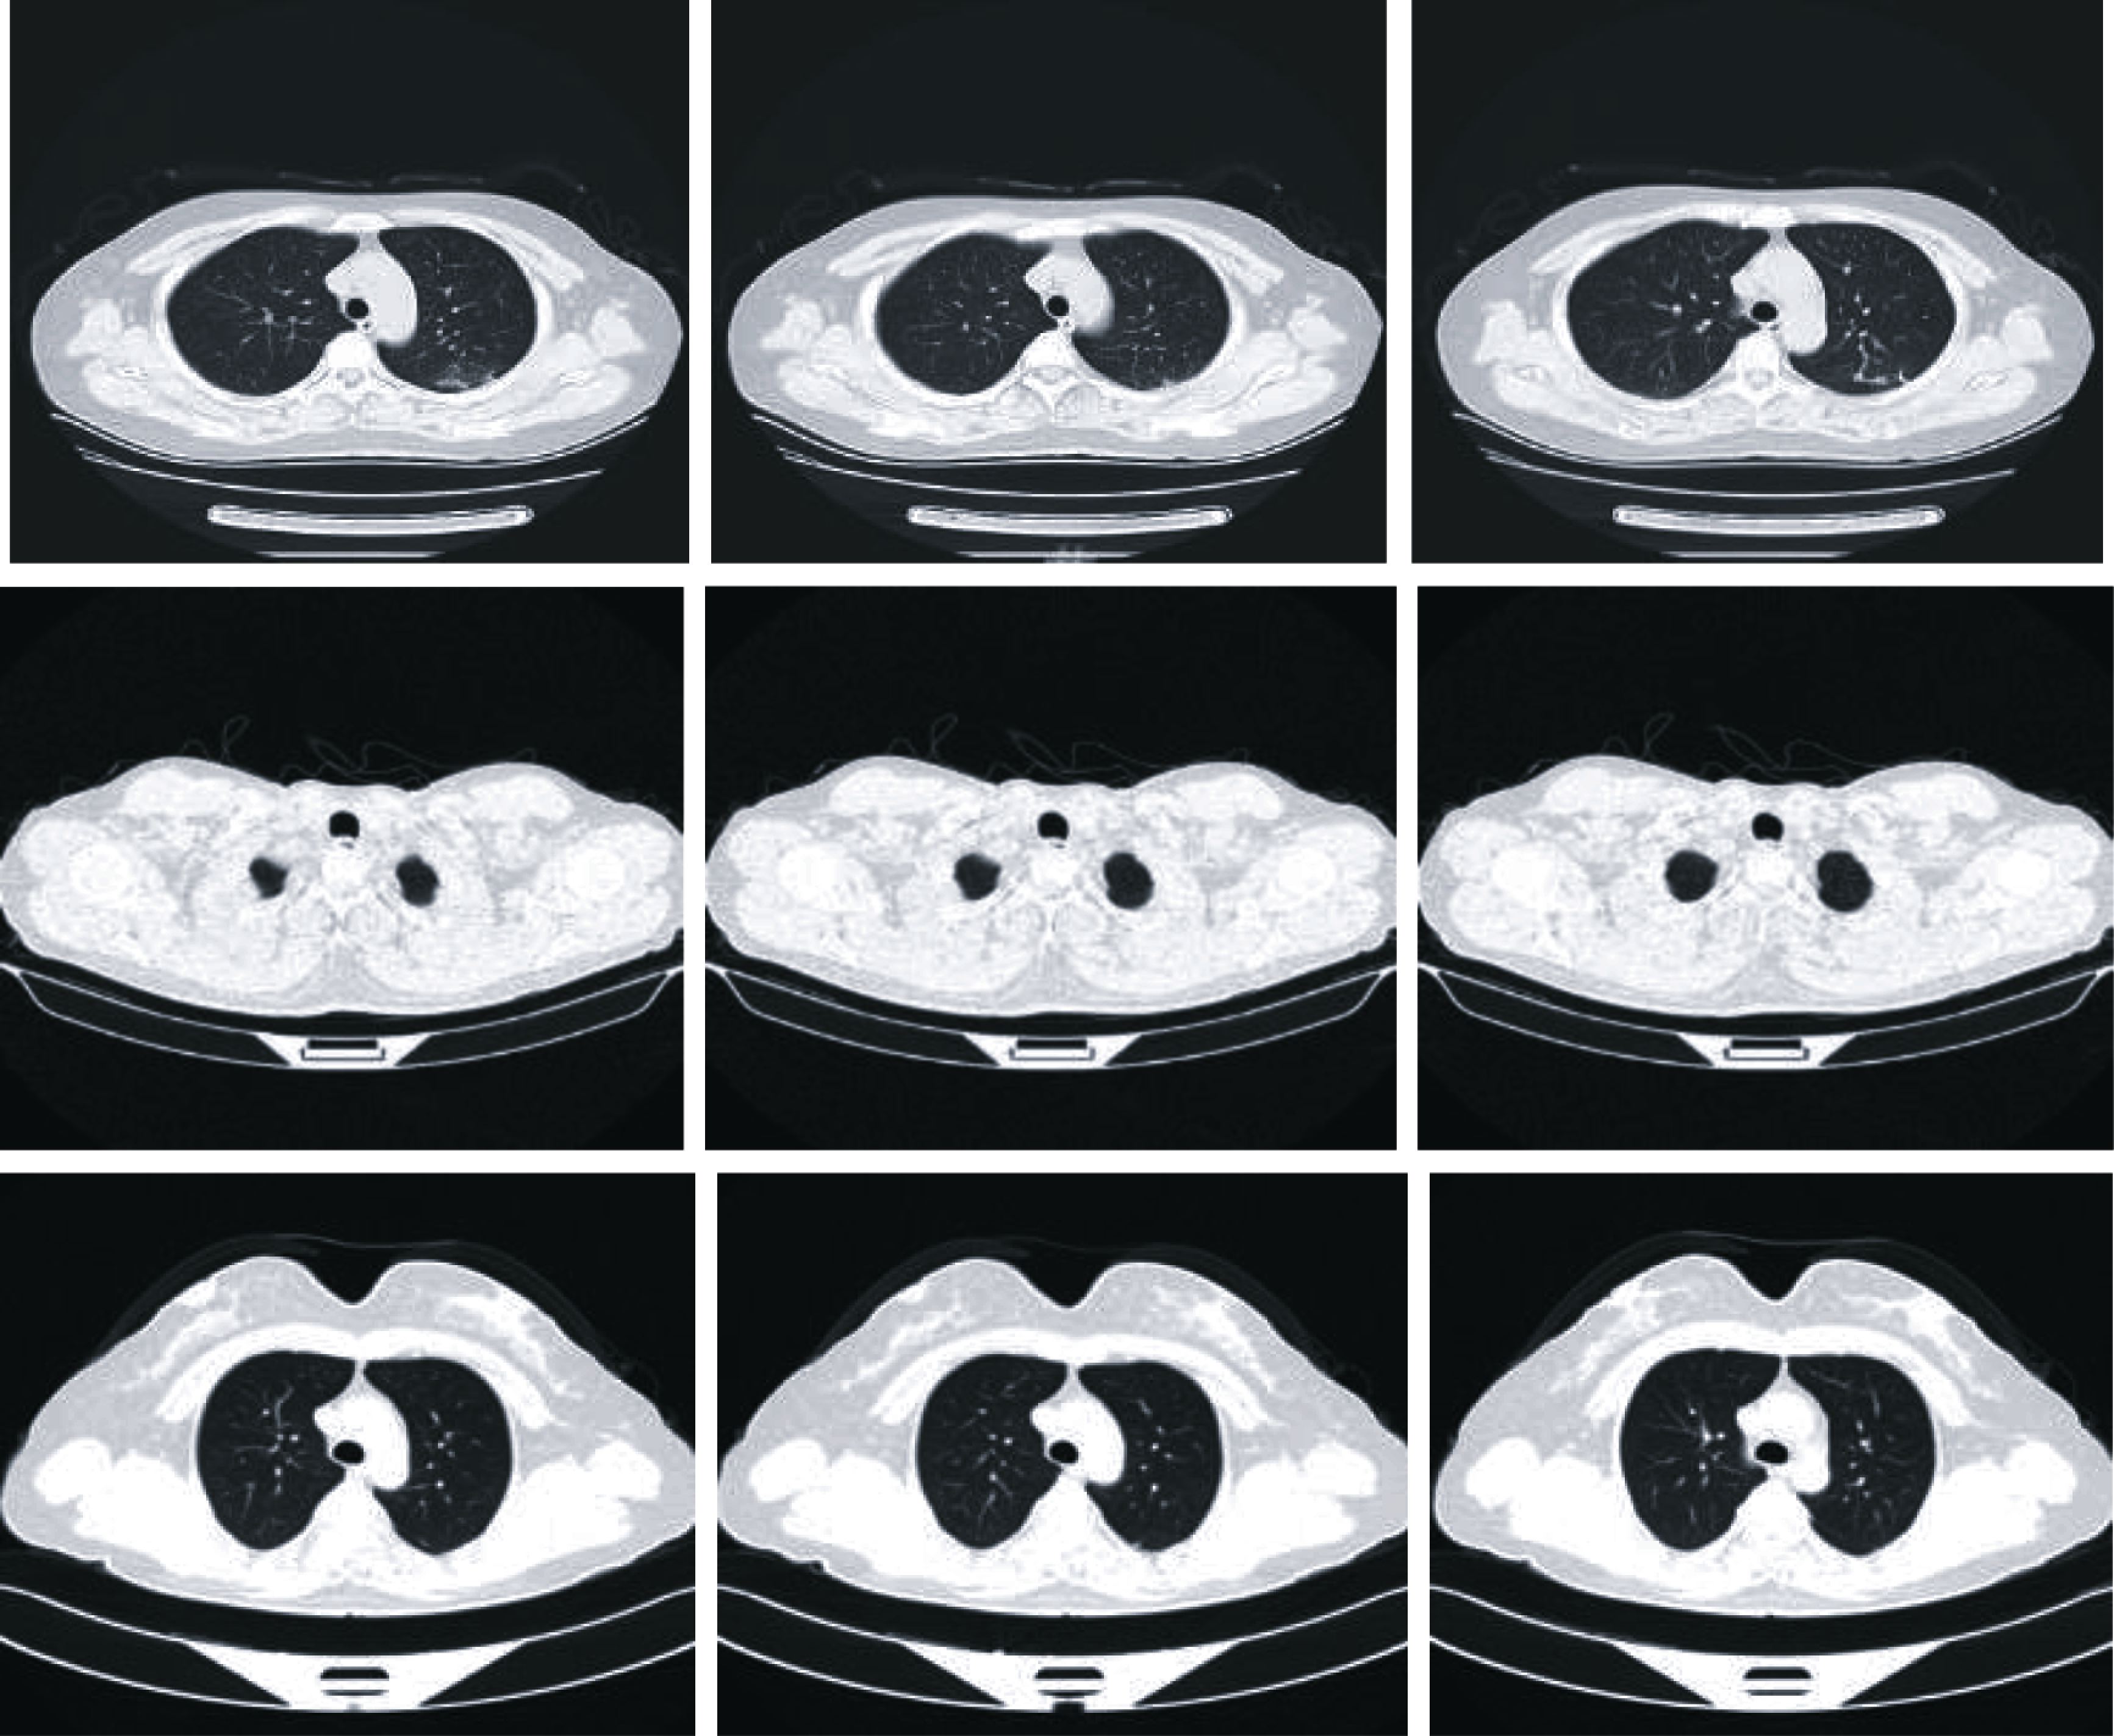

The proposed approach is performed on a data collected from Kaggle dataset [6]. The CT images are utilized to validate the proposed approach, and they are used for multi-class classification for different cases including COVID-19, pneumonia, and normal cases. The proposed approach is tested using several ratios of training and testing (80% for training and 20% for testing, 70% for training and 30% for testing, and 60% for training and 40% for testing). The proposed approach succeeds and achieves high accuracies for all examined training and testing ratios. Fig. 4 gives examples of the different considered cases.

Figure 4: Examples of the considered COVID-19, pneumonia, and normal cases